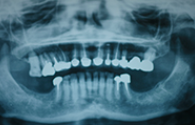

Cas cliniques

Chaque cas est unique nous essayons toujours de privilégier la meilleure solution pour le patient, d'abord d'un point de vue thérapeutique mais aussi d'un point de vue financier.

Ces cas cliniques sont une illustration pédagogique de traitements odontologiques. Leur objectif est de mettre en image des soins dentaires pour une meilleure compréhension de ceux-ci.